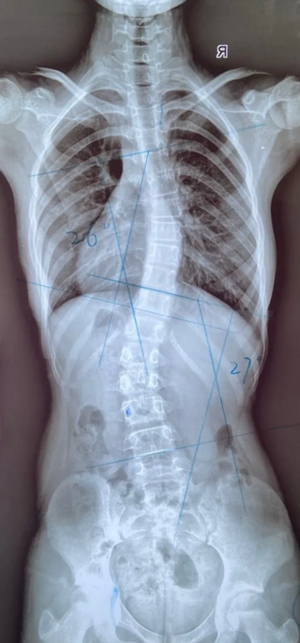

脊柱上下雙彎矯正效果

13歲女孩,2021年2月份檢查出脊柱側(cè)彎,胸26°,腰27°。制作支具后,患者沒有不舒適感,并表示愿意配合穿戴支具。每天穿戴22個(gè)小時(shí)左右,半年后,身高由150生長至153cm,脫支具24小時(shí)后拍片,側(cè)彎角度由原先胸26°,腰27°,減少至胸16°,腰17°。